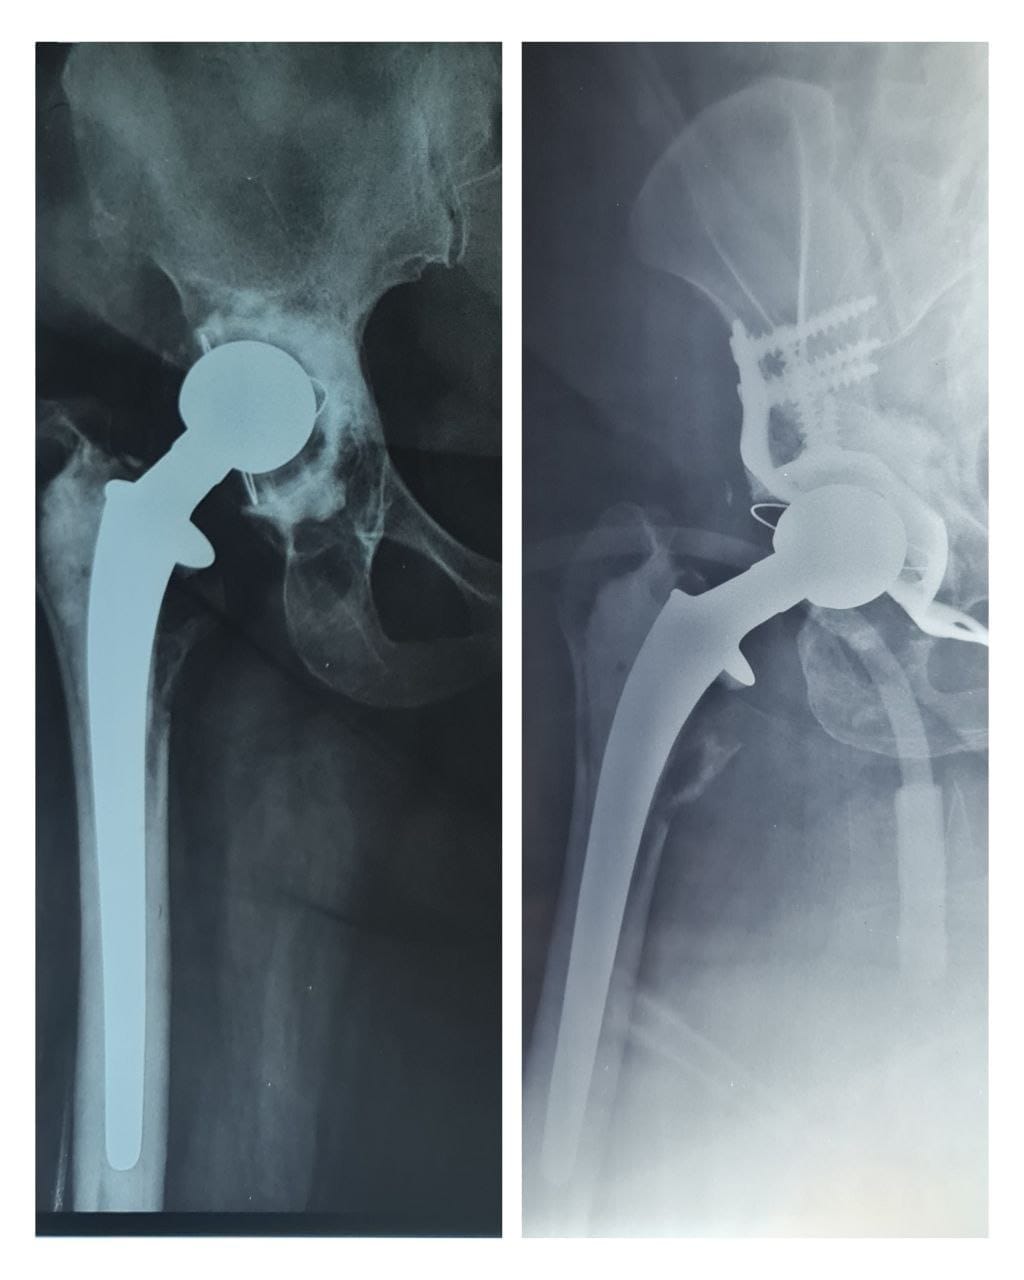

مستشفى ابن سينا تجري عملية معقدة لمريضة بعمر ٥٠ سنة

اجرى فريق طبي جراحي في مركز تبديل المفاصل والكسور المعقدة في مستشفى ابن سينا التدريبيعملية نوعية ومعقدة...